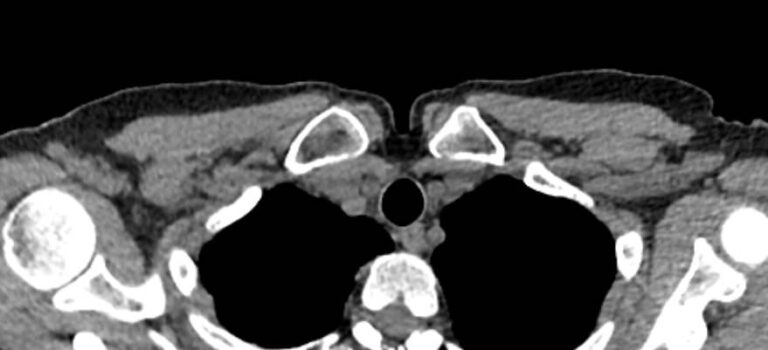

Однако классический рентген не всегда обеспечивает качественную визуализацию ГКС из-за наложения друг на друга изображений костных структур. Компьютерная томография лишена таких недостатков. При проведении КТ излучатель рентгеновских лучей совершает круговые движения вокруг исследуемой области, проводя сканирование в различных плоскостях. В результате получаются детальные снимки высокого качества, а после цифровой обработки – трехмерные модели грудино-ключичных сочленений в мельчайших подробностях.

КТ благодаря быстроте, доступности и высокой информативности часто назначается в экстренных ситуациях, например, при травмах и в случае необходимости проведения оперативного лечения. Поэтому метод особенно востребован в ортопедии и травматологии. На снимках КТ и трехмерных изображениях можно оценить состояние суставных поверхностей грудино-ключичных сочленений, а в случае перелома определить точную локализацию костных отломков.